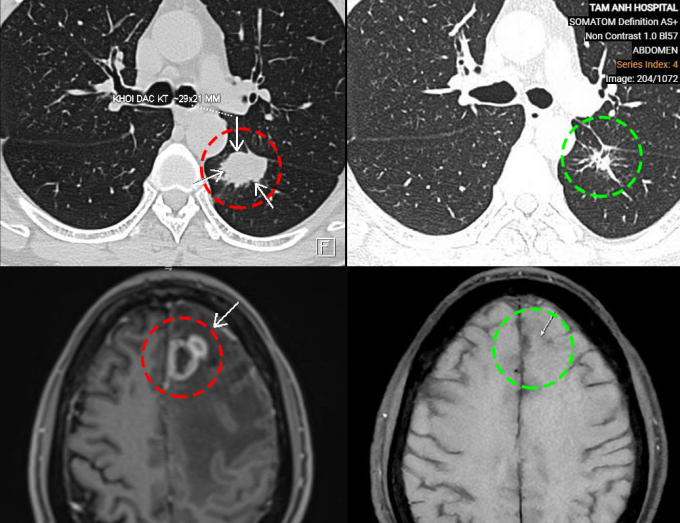

TS.BS Vũ Hữu Khiêm, Trưởng khoa Ung bướu, Bệnh viện Đa khoa Tâm Anh Hà Nội, cho biết ông Chung đến khám lần đầu vào nửa năm trước trong tình trạng yếu liệt nửa người, đi lại khó khăn, đau đầu, chóng mặt, tức ngực, khó thở. Kết quả xét nghiệm máu, chụp cộng hưởng từ não (MRI) và chụp cắt lớp vi tính (CT) ngực cho thấy khối u kích thước 21x29 mm ở thùy dưới phổi trái và khối u kích thước 30x24x21 mm ở thùy trán não trái, kèm phù não rộng xung quanh.

Ông Chung đáp ứng tốt với điều trị. Kết quả chụp MRI và CT sau 6 chu kỳ truyền thuốc miễn dịch cho thấy cả khối u thùy dưới phổi trái và khối u di căn não đều đã giảm kích thước. Tổn thương phù não không còn. Người bệnh hết đau đầu, chóng mặt, hết yếu liệt nửa người, tiếp tục duy trì phác đồ cho đến khi bệnh khỏi hoàn toàn.